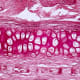

“There is a natural gradient from the top of cartilage to the bottom, where it contacts the bone,” Zlotnick explained. “Superficially, or at the surface, cartilage has a high cellularity, meaning there is a higher number of cells. But where cartilage attaches to the bone, deeper inside, its cellularity is low.”

After brief contact with the magnetic field, the hydrogel solution (and the objects in it) was exposed to ultraviolet light in a process called “photo crosslinking” to lock everything in place, and the magnetic solution subsequently was diffused out. After this, the engineered tissues maintained the necessary cellular gradient.

With this magneto-patterning technique, the team was able to recreate articular cartilage, the tissue that covers the ends of bones.